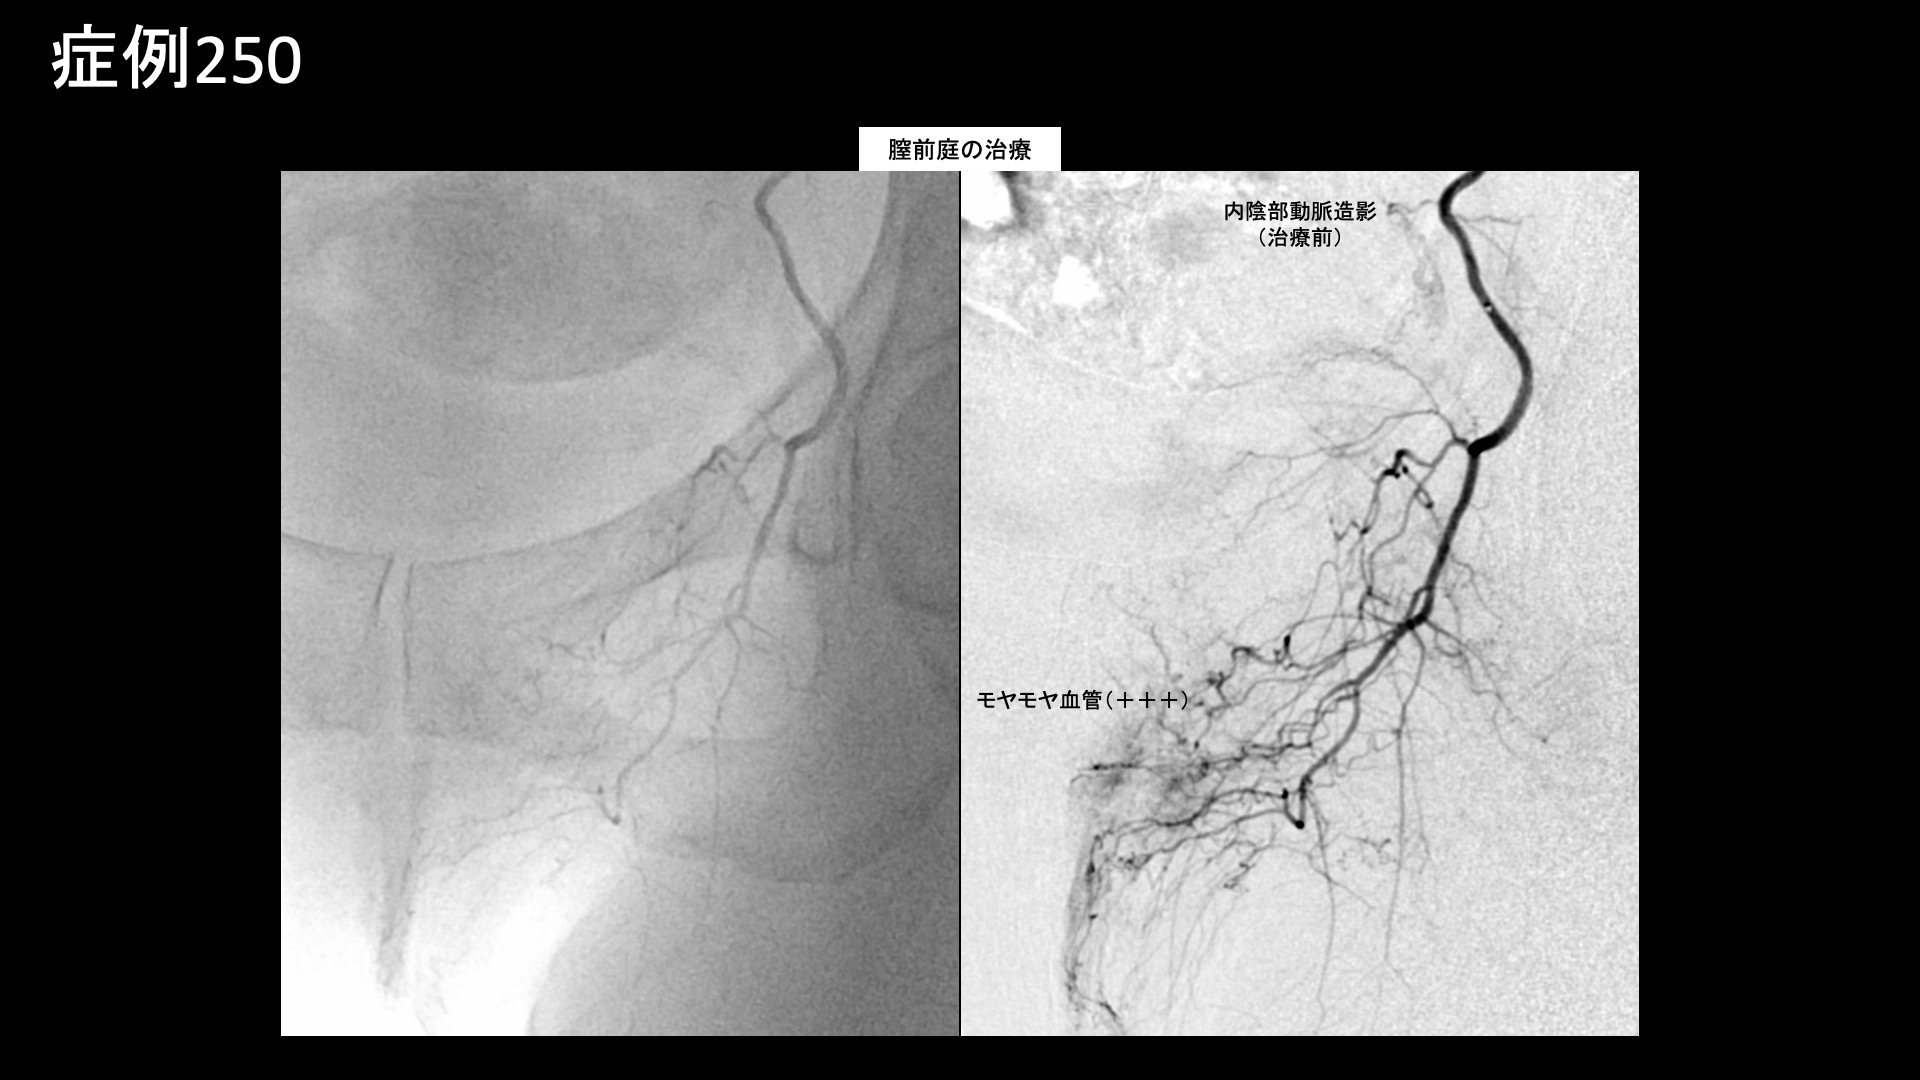

股:変形性股関節症など 【60代:女性】尿が溜まると膣が痛い!夜も寝られず。繰り返す膀胱炎から発症した間質性膀胱炎および膣前庭炎に対するモヤモヤ血管カテーテル治療(間質性膀胱炎、膣前庭炎) 2025.11.21 鴨井院長による動画解説 受診までの経過 1年前から膀胱炎を繰り返していました。最初は下腹部に痛みがありましたが、その後膣周囲など全体的に痛みが広がりました。1-2時間立っていると痛みが出てきますが、座るときにも痛みが出ます。膣の周りに針で刺されたような痛みがあり、夜間も痛みで目が覚めてしまうほどでした。ひどい時は5-6回目が覚めることもありました。トイレに行くと少し痛みが和らぎました。泌尿器科や婦人科を受診し、膀胱鏡検査を何度か受けたほか、造影MRI検査なども受けましたが特に異常所見はありませんでした。尿が溜まると膣の痛みが生じることから、間質性膀胱炎と診断されました。一方、痛みの主体は膣の入り口部分であり膣前庭炎ではないかとも思い、併せて治療目的で当院を受診されました。 診察時の所見 間質性膀胱炎に膣前庭炎が合併することは少なくありません。繰り返す膀胱炎をきっかけに広い範囲で炎症をきたした状態と考えられました。この場合、それぞれの治療を行う必要があります。治療適応と判断し、モヤモヤ血管(病的新生血管)に対する運動器カテーテル治療(微細動脈塞栓術)を受けていただきました。 治療の所見 血管造影を行うと、下膀胱動脈においてモヤモヤ血管が濃染像として豊富に描出されました。非常に強い炎症の存在が示唆されました。治療時の再現痛も強く認められました。治療後モヤモヤ血管は画像上速やかに消失しました。また、内陰部動脈では一部膣前庭に灌流する分枝があり、同部位にモヤモヤ血管が濃染像として描出されました。同様に、治療時に一定の再現痛を認めました。その他複数箇所の治療を行い終了しました。 *再現痛とは、薬液投与時に普段の痛みが一定程度再現される現象です。責任血管の同定のための参考とします。 治療前画像:損傷を受ける、あるいは繰り返しのストレスにより発生した異常な新生血管 治療後画像:カテーテルを用いて塞栓物質を血管内に投与し新生血管を塞いだ状態 治療費用:治療する部位によって費用が異なりますのでこちらをご参照ください。 主なリスク・副作用等:針を刺した場所が出血により腫れや痛みを生じたり、感染したりすることがあります(穿刺部合併症)。造影剤によるアレルギー(皮膚のかゆみ・赤み・息苦しくなるなどの症状)が出ることがあります。 治療後の経過 治療後3週間、ひどい痛みが減りました。特に日中が楽になりました。夜間に痛むものの、トイレの頻度は3-4回に減りました。術前同様、排尿後は楽でした。治療後1ヶ月になるとさらに改善が進み、全体としては6割~7割方の症状が改善しました(3-4/10程度)。夜間痛があまり生じなくなり、寝られるようになりました。その後、痛むときがありぶり返すのではないかと心配になりましたが、また改善が進み、治療後3ヶ月時点では元の症状の8割~9割方が改善しました(1-2/10程度)。まだ強く痛むことがあるにはありましたが、それでも元の痛みの半分程度でした。不安もだいぶ軽減されていました。まだ完治には至っておらず、元の炎症所見の程度を考慮すると、追加治療による改善の余地があるものと思われました。今後、ご希望があれば追加治療を検討する予定です。膣前庭炎合併の間質性膀胱炎という非常に難しい痛みを抱えておられましたが、まずはここまで改善されて何よりでした。繰り返す膀胱炎は、間質性膀胱炎や膣前庭炎を発症する要因の一つですので要注意です。 間質性膀胱炎の詳細 【50代:女性】ステロイド軟膏塗布が原因で3年以上続いた顔面酒さに対するモヤモヤ血管治療(顔面酒さ、ステロイド性皮膚炎) 前の記事 【50代:男性】最初からここに来ればよかった・・ステロイド注射無効で半年間苦しんだ石灰沈着性腱板炎による肩の痛み(石灰沈着性腱板炎、肩関節周囲炎) 次の記事